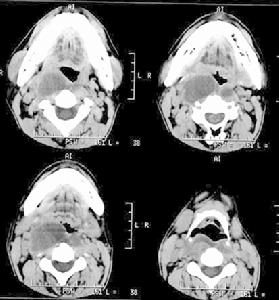

計算機體層攝影(CT) 頸椎CT能顯示椎體甚至附屬檔案的微小病灶。多採用橫斷面掃描。CT平掃骨窗可顯示椎體的骨質破壞呈椎體密度不均,其內可見片狀高密度影,有時呈擰碎的餅乾屑樣。並可顯示骨質嚴重破壞導致椎體塌陷、後突和椎管狹窄。頸椎結核的膿腫常出現於椎前,CT平掃顯示為密度略低的椎前腫塊,CT值提示為液性密度,不均勻。增強後膿腫周緣有環狀強化。慢性膿腫內可出現高密度的鈣化影。CT還可發現椎管內硬膜外的膿腫,椎管碘水造影后CT顯示更清楚。寰樞椎結核患者多有斜頸畸形,X線平片較難顯示病灶,CT平掃骨窗可顯示環椎的前弓、側塊骨質破壞,樞椎的齒狀突椎體骨質破壞,還可顯示寰樞關節前脫位及椎旁咽後膿腫。CT三維重建則更有利於觀察結核引起的齒狀突鏇轉關脫位,寰椎側方半脫位及椎管狹窄狀況。CT三維重建還有利於觀察枕骨大孔與寰樞複合體因結核病灶破壞而發生的相鄰關係的改變。